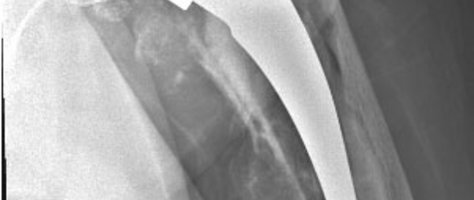

Für spezielle Situationen wie Prothesenlockerungen oder Frakturen im Bereich des künstlichen Gelenkes stehen besondere, modulare Prothesen zur Verfügung. Diese lassen sich speziell an die jeweilige Situation anpassen. Bei jüngeren Patienten wird hier die zementfreie Technik bevorzugt, weil sich eventuelle Wechseloperationen (keine Prothese hält für immer) später leichter durchführen lassen.

In besonderen Situationen, z.B. bei sehr alten Patienten, kann eine zementierte Prothesenversion sinnvoller sein, weil diese in der Regel sofort belastet werden können und eine Wechseloperation unwahrscheinlich ist.